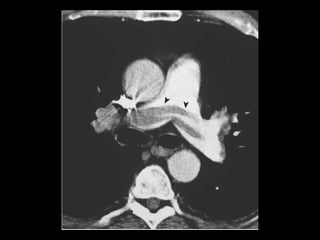

Embolia Pulmonar Patologiacomum e representa a terceira causa de morte nos EUA; Resulta de um trombo formado nos sistema venoso; Radiografia de tórax tem valor limitado: tem mais valor em excluir outras condições; Exame de escolha: angio-TC(MD); Acurácia da TCMD depende: do tamanho da artéria afetada e do tamanho do êmbolo;

Embolia Pulmonar Diagnóstico deembolia aguda na TC com contraste é baseado na visualização direta de falhas de enchimento parciais ou completas dentro das artérias pulmonares; Sinal da “rosca”; Sinal do “trilho de trem”; Outro sinal útil: formação de ângulos agudos com a parede vascular, a perda completa da opacificação e o aumento do diâmetro do vaso acometido.